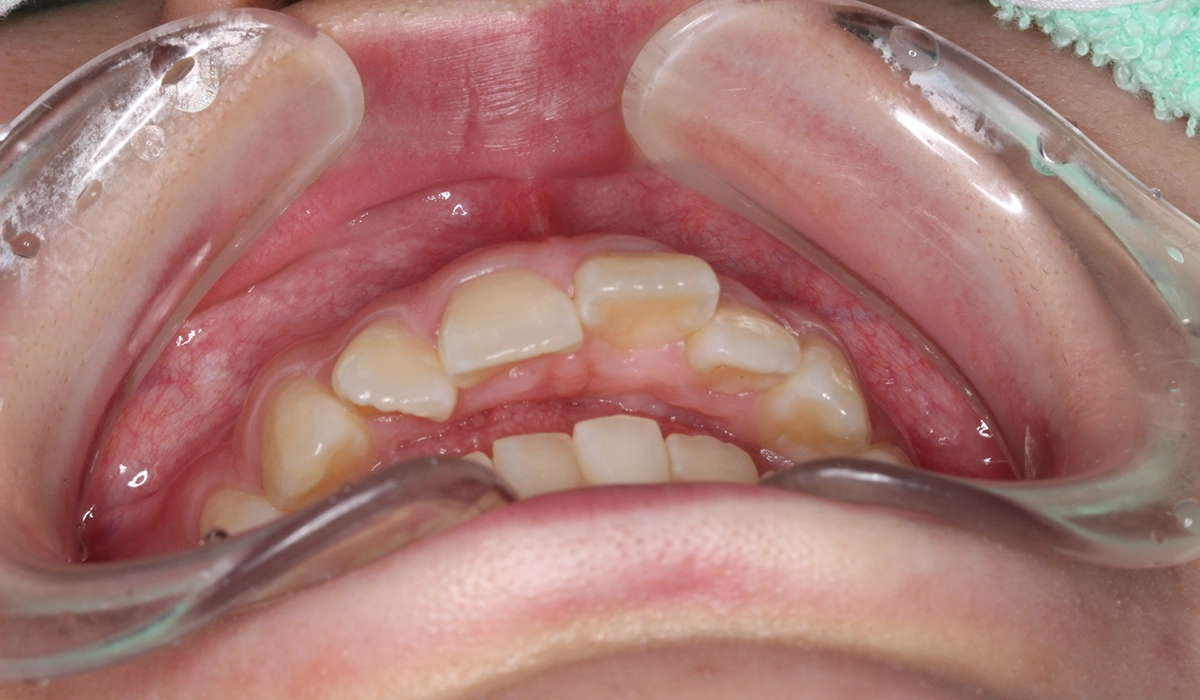

術前:前歯部

術後:前歯部